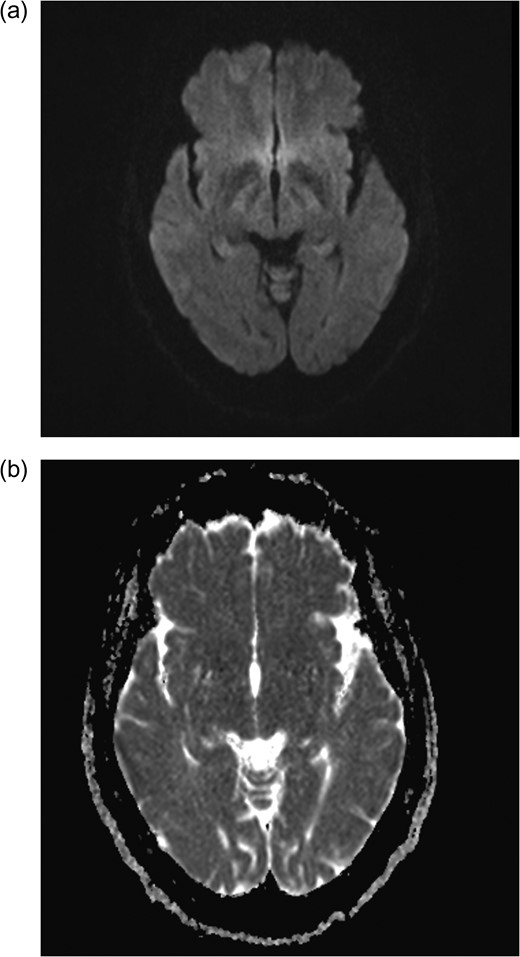

Axial MRI brain (a) diffusion weighted imaging (DWI) and (b) apparent diffusion coefficient (ADC) demonstrating no restricted diffusion.